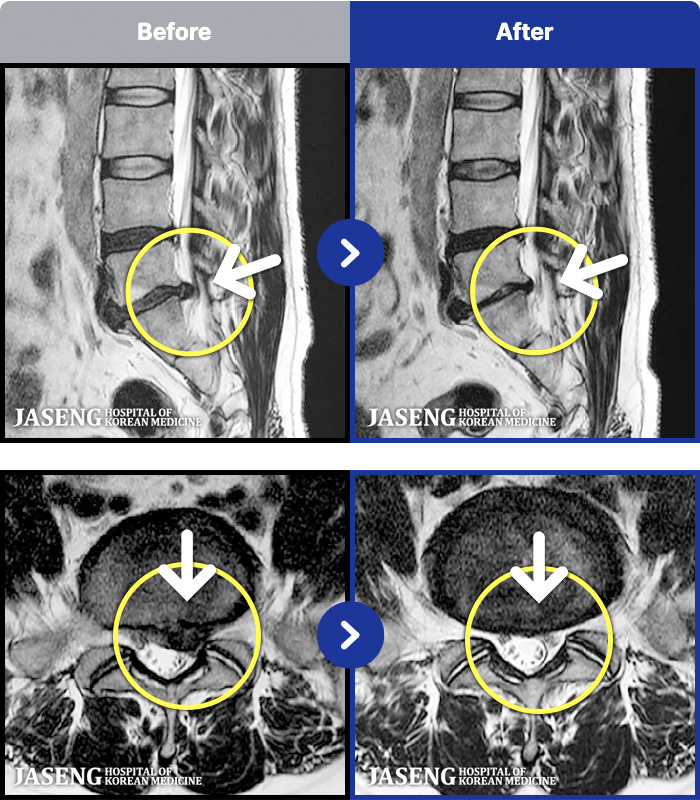

191 MRI ũ ʸ Ȯϼ.

ȯںп Ǹ ǿ ԿǾ, ο ġ ۿ Ƿ ġḦ Ͻñ ٶϴ.